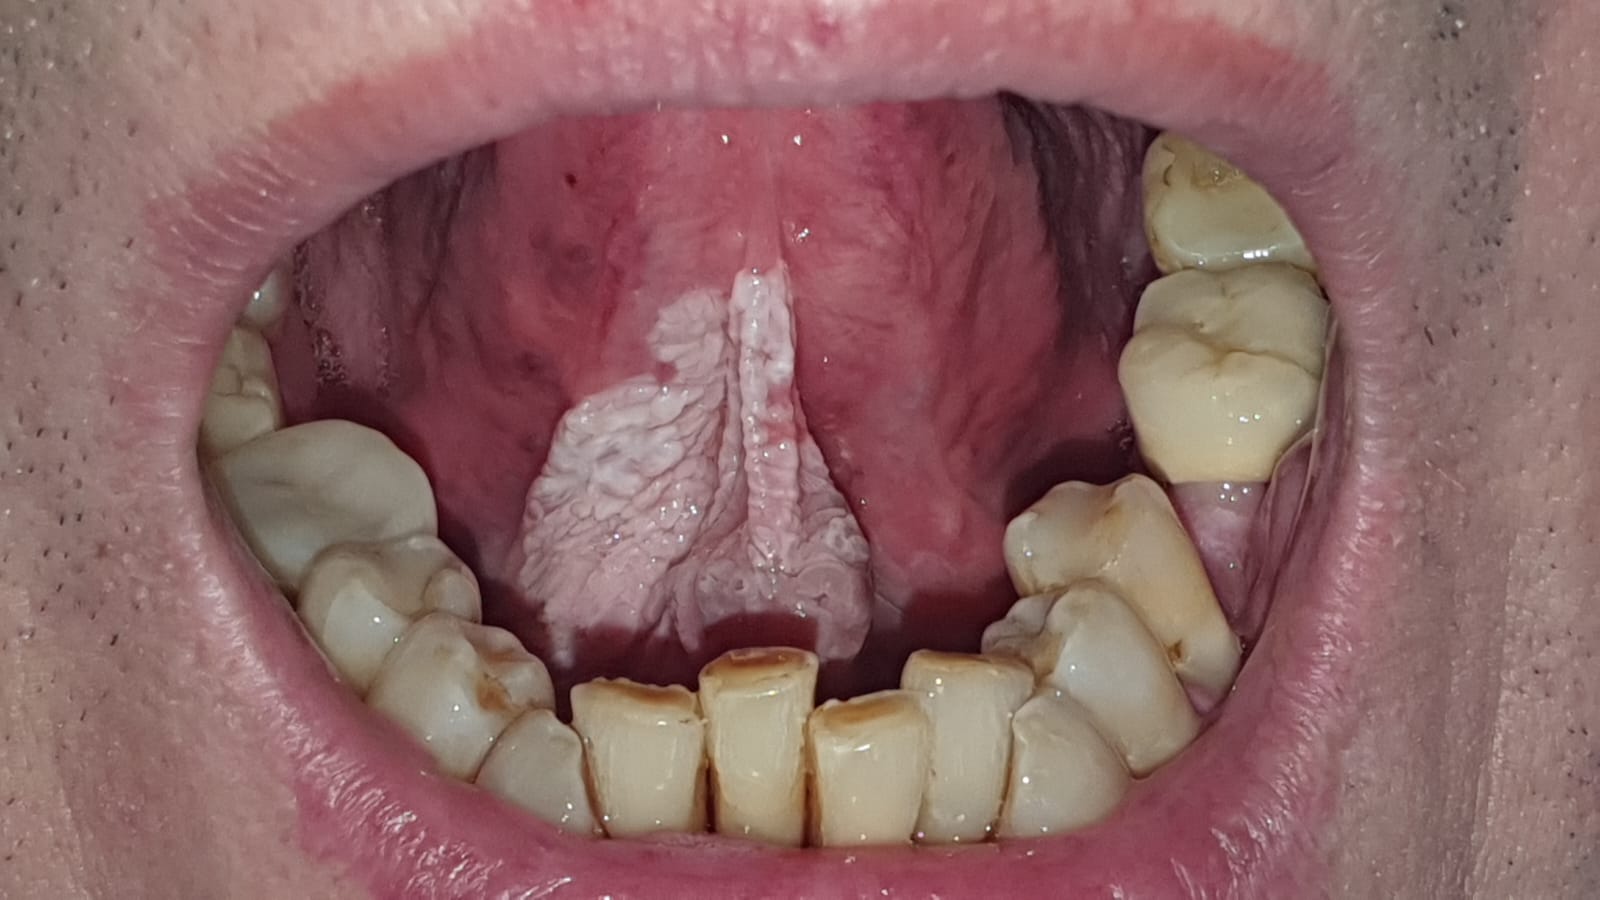

Leukoplakia to jedna z najczęstszych zmian przednowotworowych w obrębie jamy ustnej (o zwiększonym ryzyku wystąpienia nowotworu złośliwego). Charakteryzuje się obecnością białych/szarych plam lub smug na powierzchni błony śluzowej.

Poniżej prezentujemy leczenie i usunięcie leukoplakii, hyperkeratozy dna jamy ustnej i brzusznej części języka laserem CO2.

Przed leczeniem